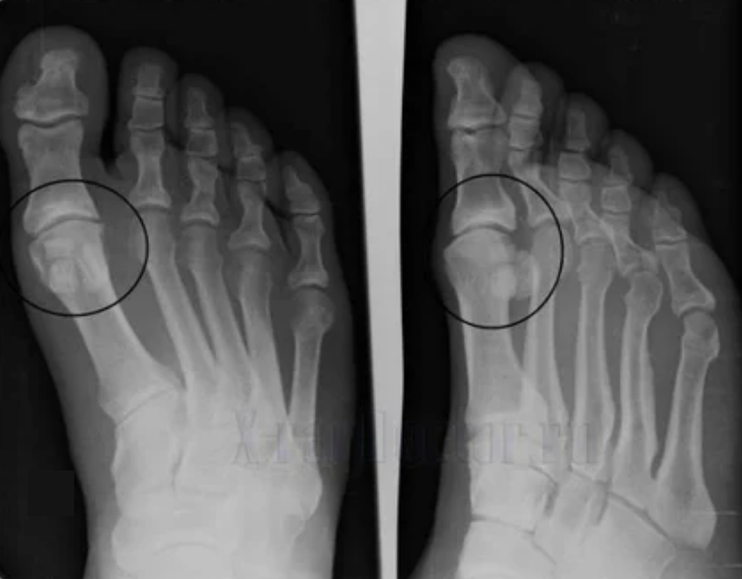

To make a diagnosis, rheumatologists study the patient's complaints and prescribe the X -Ray examination.The most common radiography is used in 2 projections.The doctor looks at the presence of dystrophic disorders in the hyaline wrists of cartilage and bones.If the articular gap is reduced, bones are deformed or flattened, there are cystic formations on the surface of the cartilage, osteofits are obvious signs of arthrosis.During the inspection, Arthrosis indicates the instability of the joint: OSA limbs and subbruxation is disturbed.

Often the X -Ray image is unable to give complete information about the condition of the wrist.For a more detailed study, calculated tomography is prescribed, it is effective for bone testing.The MRI is more commonly used to study soft tissues.